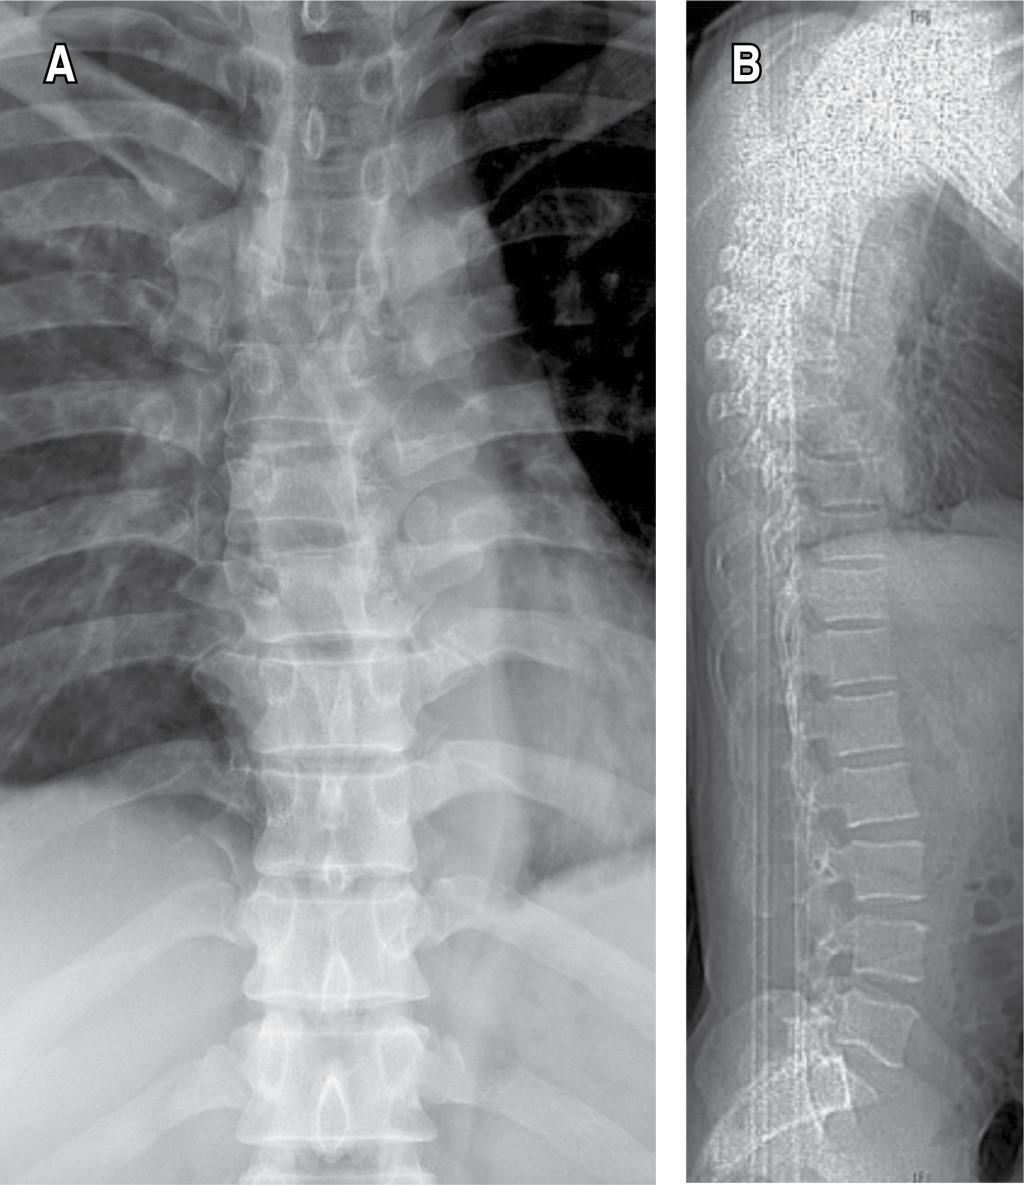

Figure 4